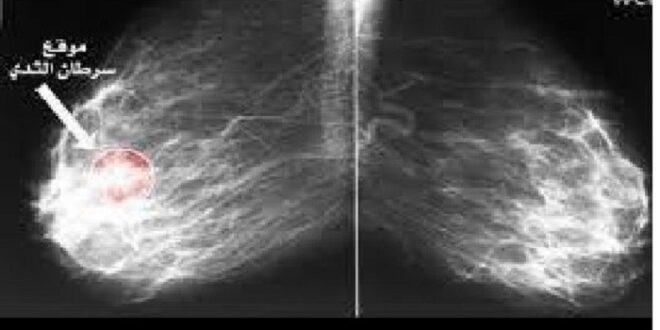

هـ ـذا المشـ ـروب الخـ ـطـ ـير نشـ ـربه كـ ـل يـ ـوم ولا نعلـ ـم أنـ ـه يسـ ـبب سـ ـرطـ ـان الثـ ـدي

مرض سرطان الثدي من الأمراض التي أصـ.ـبحت منتـ.ـشرة بشكل كبير، ولكن الأهم هل تعلمون السبب في انتشار هذا المـ.ـرض بهذا…